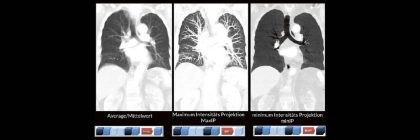

Professor Dr. med. Marc Brockmann WEITERENTWICKLUNGEN VON KOPF BIS FUSS BEIM VC Oberstarzt Dr. med. Stephan Waldeck DEEP-LEARNING-REKONSTRUKTION IN DER NEURORADIOLOGIE Die CT ist ein essentielles Routine-Verfahren in der Neuroradiologie. Weiterlesen …